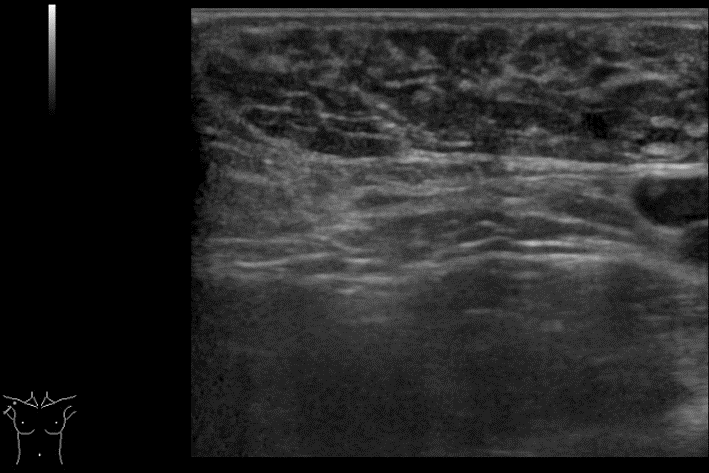

線維腺腫(陳旧性線維腺腫)